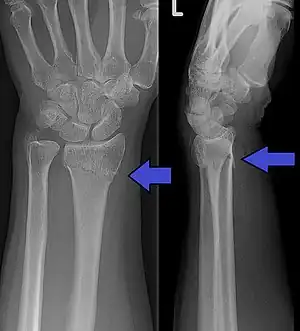

A Colles fracture as seen on X-ray: It is a type of distal radius fracture.